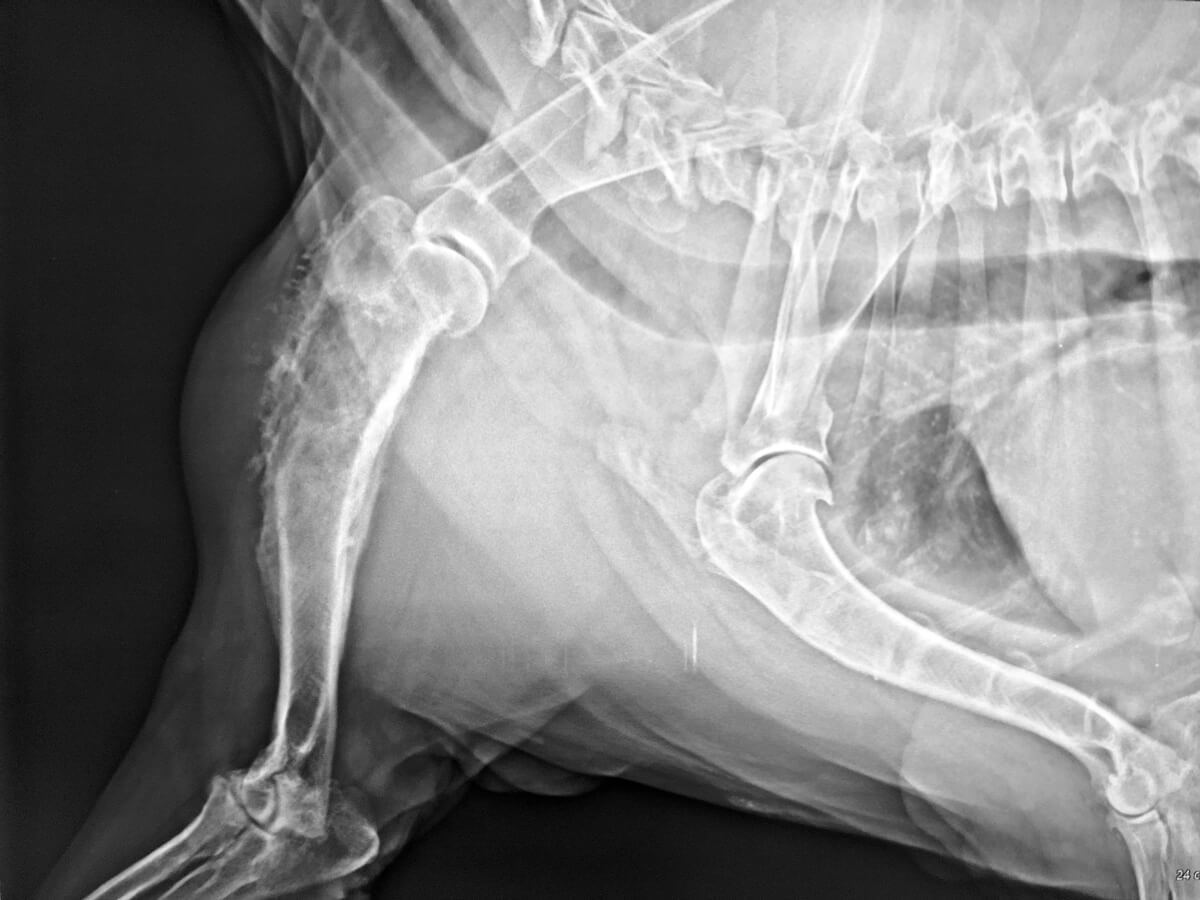

La bursitis por infección en perros es la inflamación de la bolsa sinovial por acción de un agente infeccioso. Si afecta a la zona del codo, también se la conoce por el nombre de bursitis olecraniana, en referencia al nombre de una porción del hueso cúbito.

- Las más superficiales se encuentran adyacentes a diferentes articulaciones, con una localización subcutánea. En caso de estar inflamadas, su alteración se observa a simple vista, como la bursa olecraniana.

Aunque se ven con mayor frecuencia en el área de los codos, estas hinchazones pueden ocurrir sobre cualquier otra articulación del cuerpo del perro. Inicialmente son inflamaciones pequeñas y suaves, pero con el tiempo pueden volverse grandes y duras.

En estos casos hay calor, dolor, inflamación periférica y una cojera severa, a veces incluso de grado cuatro. Esta bursitis es evidente al afectar el paso normal del perro y producir dificultad para apoyar la extremidad afectada con normalidad.